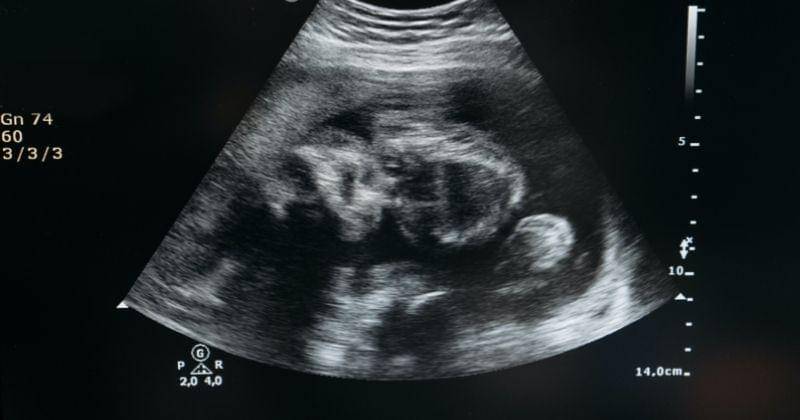

Salah satu yang paling banyak ditakuti ibu hamil adalah janin yang terlilit tali pusar (nuchal cord), sehingga mengakibatkan berbagai masalah selama hamil hingga persalinan.

Jika tidak diketahui sejak dini, kondisi ini memang cukup membahayakan, terutama jika janin mengalami lebih dari satu lilitan.

Itulah tanda-tanda janin terlilit tali pusar. Mengetahui hal ini sejak dini akan dapat menurunkan risiko dan bahaya yang ditimbulkan. Karenanya, jangan ragu memeriksakan diri ke dokter karena 70 persen kasus nuchal cord biasanya diketahui saat Mama menjalani USG.